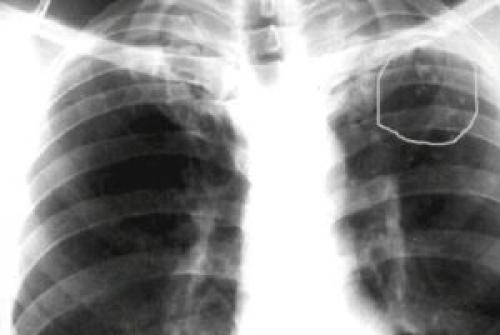

При плановой флюорографии на изображении лёгких и его тканей, отраженных от светящегося экрана,становятся видны округлые тени на фоне бледной легочной ткани (плотность кальцинатов можно сравнить с плотностью кости).

Чаще обнаруживается не один, а несколько таких очагов. Они могут быть разными по размеру и форме.

Ведь под кальцинат может маскироваться костная мозоль ребра, активное развитие туберкулезного процесса, даже онкологическое заболевание.